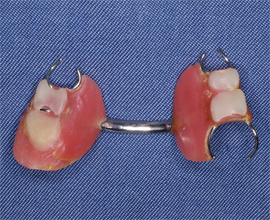

患者が以前使用していた義歯 患者が以前使用していた義歯

図2a 患者が以前使用していた義歯

図2b 患者が以前使用していた義歯

患者が使用中の義歯 最終義歯

図2c 患者が使用中の義歯

図2d 最終義歯

図2a~cはその患者が持参した義歯である.3つの義歯のうち図2cのものを現在使用している.ほかの2つの義歯を使用しているときには食べることに不自由がなかったが現義歯になってから食べづらくなったとのことである.図2dは最終義歯を装着したときに口腔内写真である.設計自体は右側4番のクラスプを変更したものの大きな設計の変更はしていないが,最終印象を行う前に支台歯に対して適切な前処置を行った. これらの症例は最終的に患者は快適に義歯を使用している。